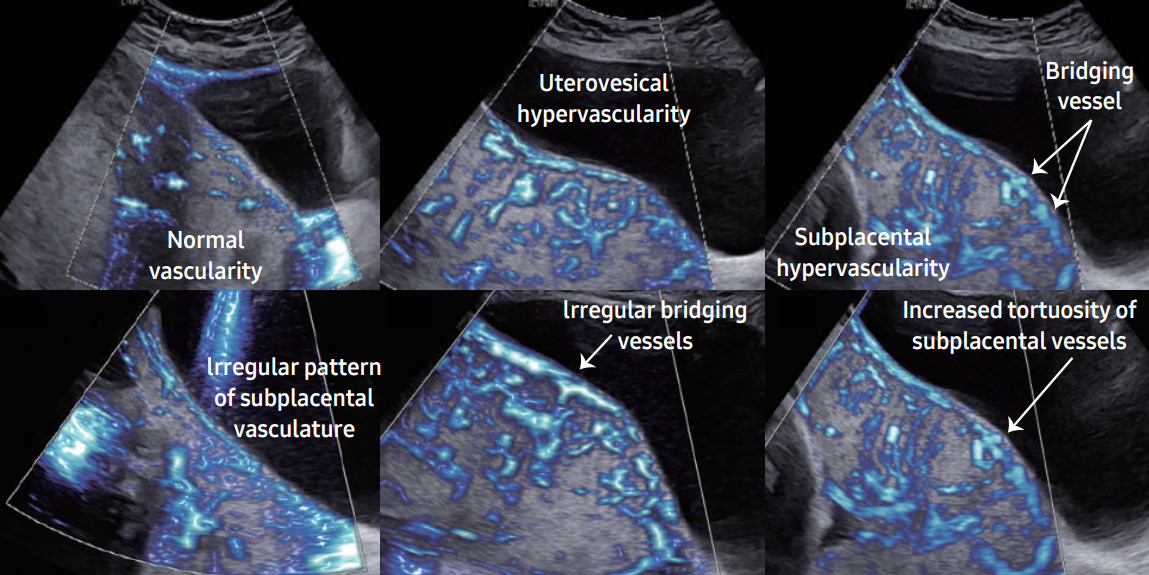

Другой способ оценки, визуализации и диагностики Placenta accreta spectrum (PAS) в системах Samsung использует аномальную гиперваскуляризацию и сложные сосудистые сети в плаценте, параметрии и маточно-пузырном интерфейсе. MV-Flow и LumiFlow — это недавно разработанные допплеровские технологии, способные обеспечить детальное представление о кровотоке по отношению к окружающим тканям в качестве альтернативы энергетическому допплеру для визуализации микроциркуляторных структур с медленным кровотоком сосудистых соединений.

Технология MV-Flow характеризуется высокой степенью уменьшения сигналов тканевого шума, подавлением артефактов вспышки, составными изображениями и высокой чувствительностью. Все это способствует оптимизации визуализации структур с низкой скоростью потока. LumiFlow помогает интуитивно отображать структуру кровотока и мелких сосудов, обеспечивая псевдотрехмерную визуализацию кровотока в двухмерном изображении за счет стереоскопического эффекта. Эта функция высокого разрешения доступна в сочетании со всеми допплеровскими технологиями, позволяющими реалистично оценивать сосудистый поток. Такие технологии могли бы помочь в визуализации сосудистых сетей на маточно-пузырной границе, параметрии и плаценте.